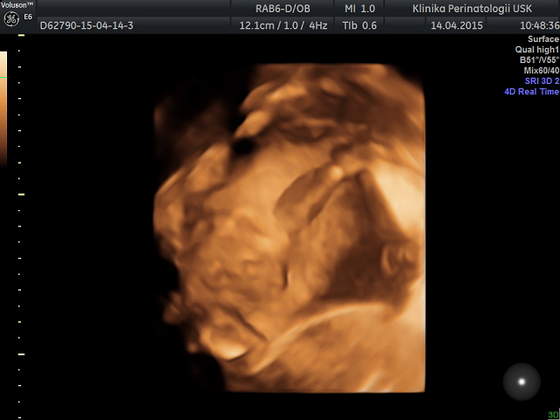

Ja też dziś miałam usg ale to młodzi doktorzy robili, więc bez szczegółów... mieli problem ze złapaniem czegokolwiek ale kawałek twarzyczki widać, szkoda tylko że nóżek nie chciał rozłożyć żeby pisiorka pokazać

a to Tymonek 24t 4d